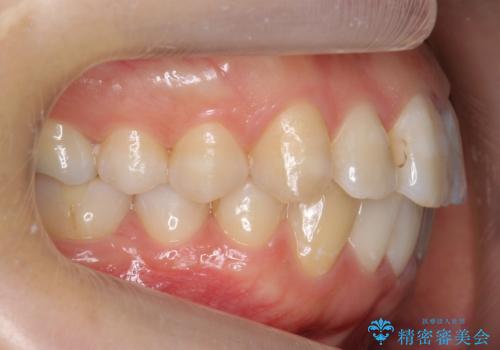

- 歯並びを主訴に来院。

左上2番は以前抜歯したとのこと。

奥歯を後ろに下げて、前歯を並べています。

マウスピースと矯正用のミニスクリューを使用して治療しています。

銀歯も白くということでしたので虫歯治療も一緒に行っています。

左上7の根の治療や左下56銀歯の治療なども行いました。